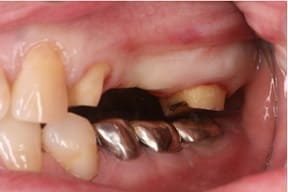

CASE03 臼歯部インプラント ~ブリッジがグラつき始めている~

ブリッジの部分の下顎の骨が吸収をおこし、ブリッジで支えている歯がぐらつき始めている状態。予後を考えた結果、ブリッジで支えることが困難という診断のもと、インプラント治療を施したケースです。